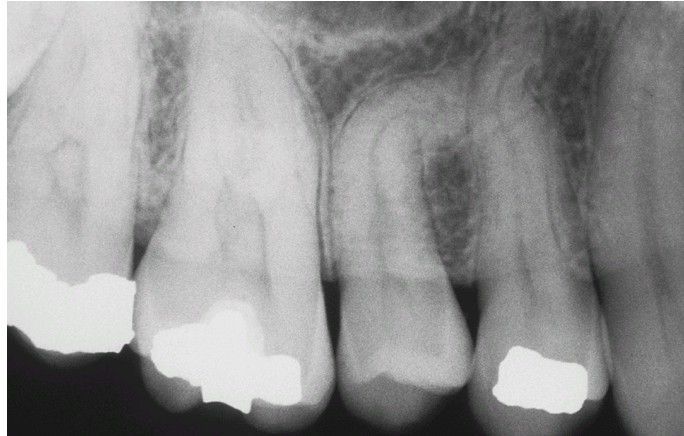

Dilaceration

. Maxillary second bicuspid exhibiting mesial inclination of the root. The patient reported no history of injury to this area.